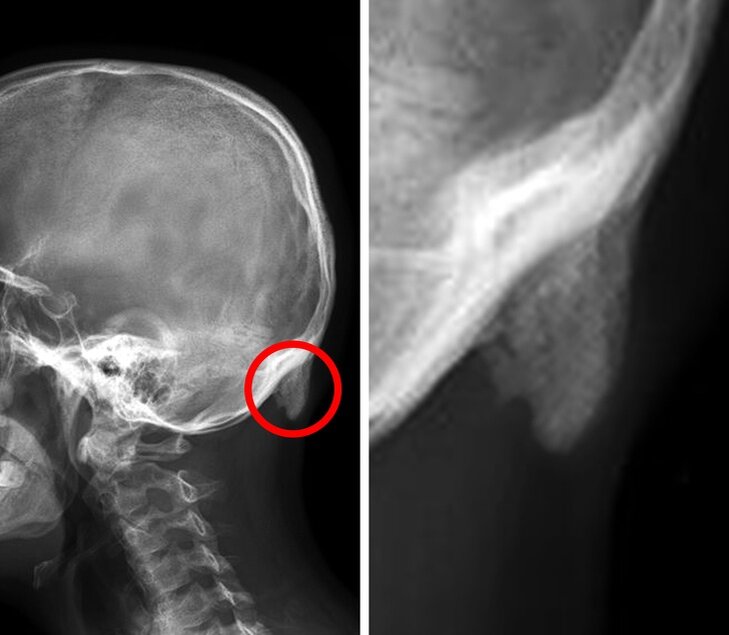

Отросток отчётливо виден на рентгеновском снимке

Благодаря проведенным исследованиям (в эксперименте участвовало порядка 218 человек разных возрастных категорий) у 41% участвующих в эксперименте было выявлен небольшой отросток на затылке размером 10мм

У некоторых данный отросток достигал 35,7 мм и 25,5 мм (в первом случае у мужчин во втором у женщин)